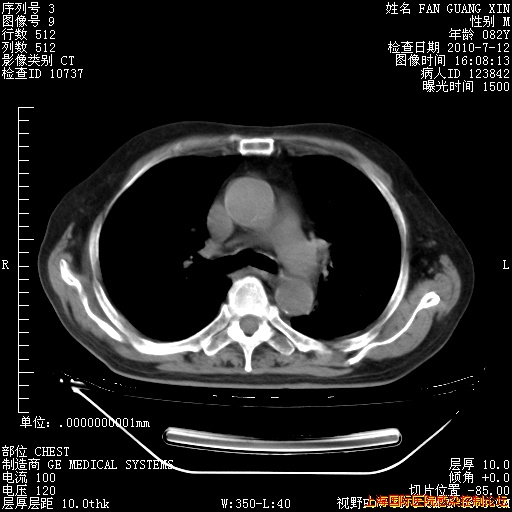

今天复查CT

今天CT

整整相隔30天的肺部CT好像有所好转啊。甲强龙减量第3天,需要观察体温。